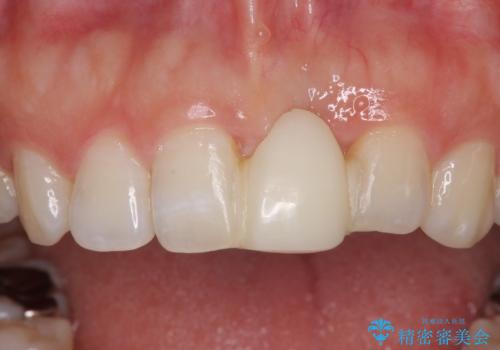

- 接着タイプの前歯のブリッジが不自然であるとのことで来院された患者様です。

欠損部の歯肉が窪んでいるため、歯肉移植により形態を改善し、オールセラミックブリッジにて補綴することとしました。

事前に装着されていた接着タイプのブリッジは、歯の切削量が少ない反面、接着界面から虫歯が進行しやすく、脱落リスクが高くなるというデメリットがあります。